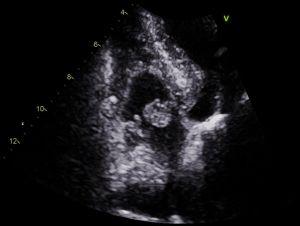

An echocardiogram is often requested for patients experiencing chest pain, and this imaging modality lends itself perfectly for the detection of myxomas.

Above: a rare finding of a myxoma on the right side of the heart in a patient referred for a suspected myocardial infarction. In this instance, the myxoma moves with opening of the tricuspid valve into the right ventricle during diastole, and returns to the right atrium during (ventricular) systole. This can be appreciated from the images below, where the image on the left is taken in diastole, and the image on the right during systole: